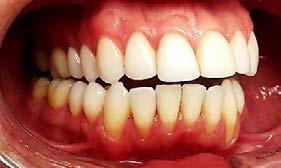

Entre los elementos que conforman al sistema estomatognático, están los dientes caninos, órganos dentales esenciales en la fisiología masticatoria; punto de unión y continuidad estética entre la línea de la sonrisa y el corredor posterior del arco dental, además de que ejercen la función de pilares estabilizadores en la oclusión fisiológica (Figura 1).

Los caninos son indispensables durante los movimientos de lateralidad y vitales para la continuidad de los arcos dentales, tanto en la dentición decidua como en la permanente; son responsables del funcionamiento y la armonía oclusal. Su posición adecuada en el arco asegura un buen contorno de la cara, sonrisa agradable y armónica con la estética facial. (Figura 2).